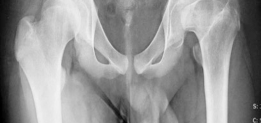

The hallmark pathoanatomy addressed by this procedure is coxa magna, characterized by an enlarged, often flattened, and extruded femoral head that results in hinge abduction and severe femoroacetabular impingement. Epidemiologically, the sequelae of childhood hip disorders present a significant burden, with untreated or severe Legg-Calvé-Perthes disease leading to premature osteoarthritis in the third or fourth decade of life. By surgically reducing the volume and reshaping the geometry of the deformed femoral head, orthopedic surgeons can re-establish a functional articulation within the native acetabulum. This conservative, albeit technically demanding, approach relies heavily on the principles of safe surgical dislocation of the hip, allowing for global access to the femoral head without compromising its tenuous vascular supply.

In the setting of coxa magna or severe cam deformity, the biomechanics of the hip are profoundly altered. The aspherical femoral head creates an abnormal center of rotation and leads to non-concentric articulation. During abduction, the enlarged lateral portion of the femoral head hinges against the lateral acetabular rim, a phenomenon known as hinge abduction. This hinging levers the medial femoral head out of the acetabulum, exponentially increasing contact pressures on the lateral compartment and leading to rapid articular cartilage degradation.

Radiographic evaluation must demonstrate a clear structural conflict, such as an extruded lateral head segment causing hinge abduction, but without advanced joint space narrowing. The presence of a "hinge" can often be confirmed dynamically under fluoroscopy or via abduction-internal rotation plain radiographs.